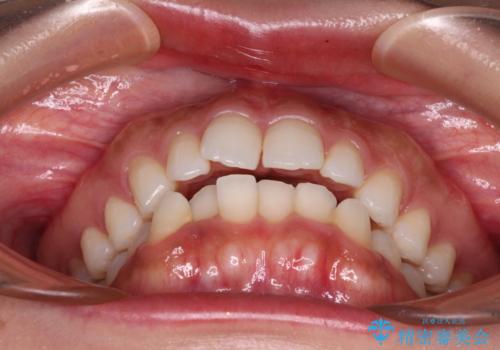

- 唇が閉じにくく、上の前歯が下唇に当たって気になるとのことで来院された患者様です。

レントゲン写真での分析結果からは、抜歯矯正をするかどうか悩む境界線上でしたが、主訴が口元の突出感であったため、上下左右の第一小臼歯4本を抜歯して矯正治療を行うこととしました。

上下ともに前歯が少し舌側に傾斜したような仕上がりとなりましたが、口が閉じやすくなったとのことで、患者様には大変満足していただけました。